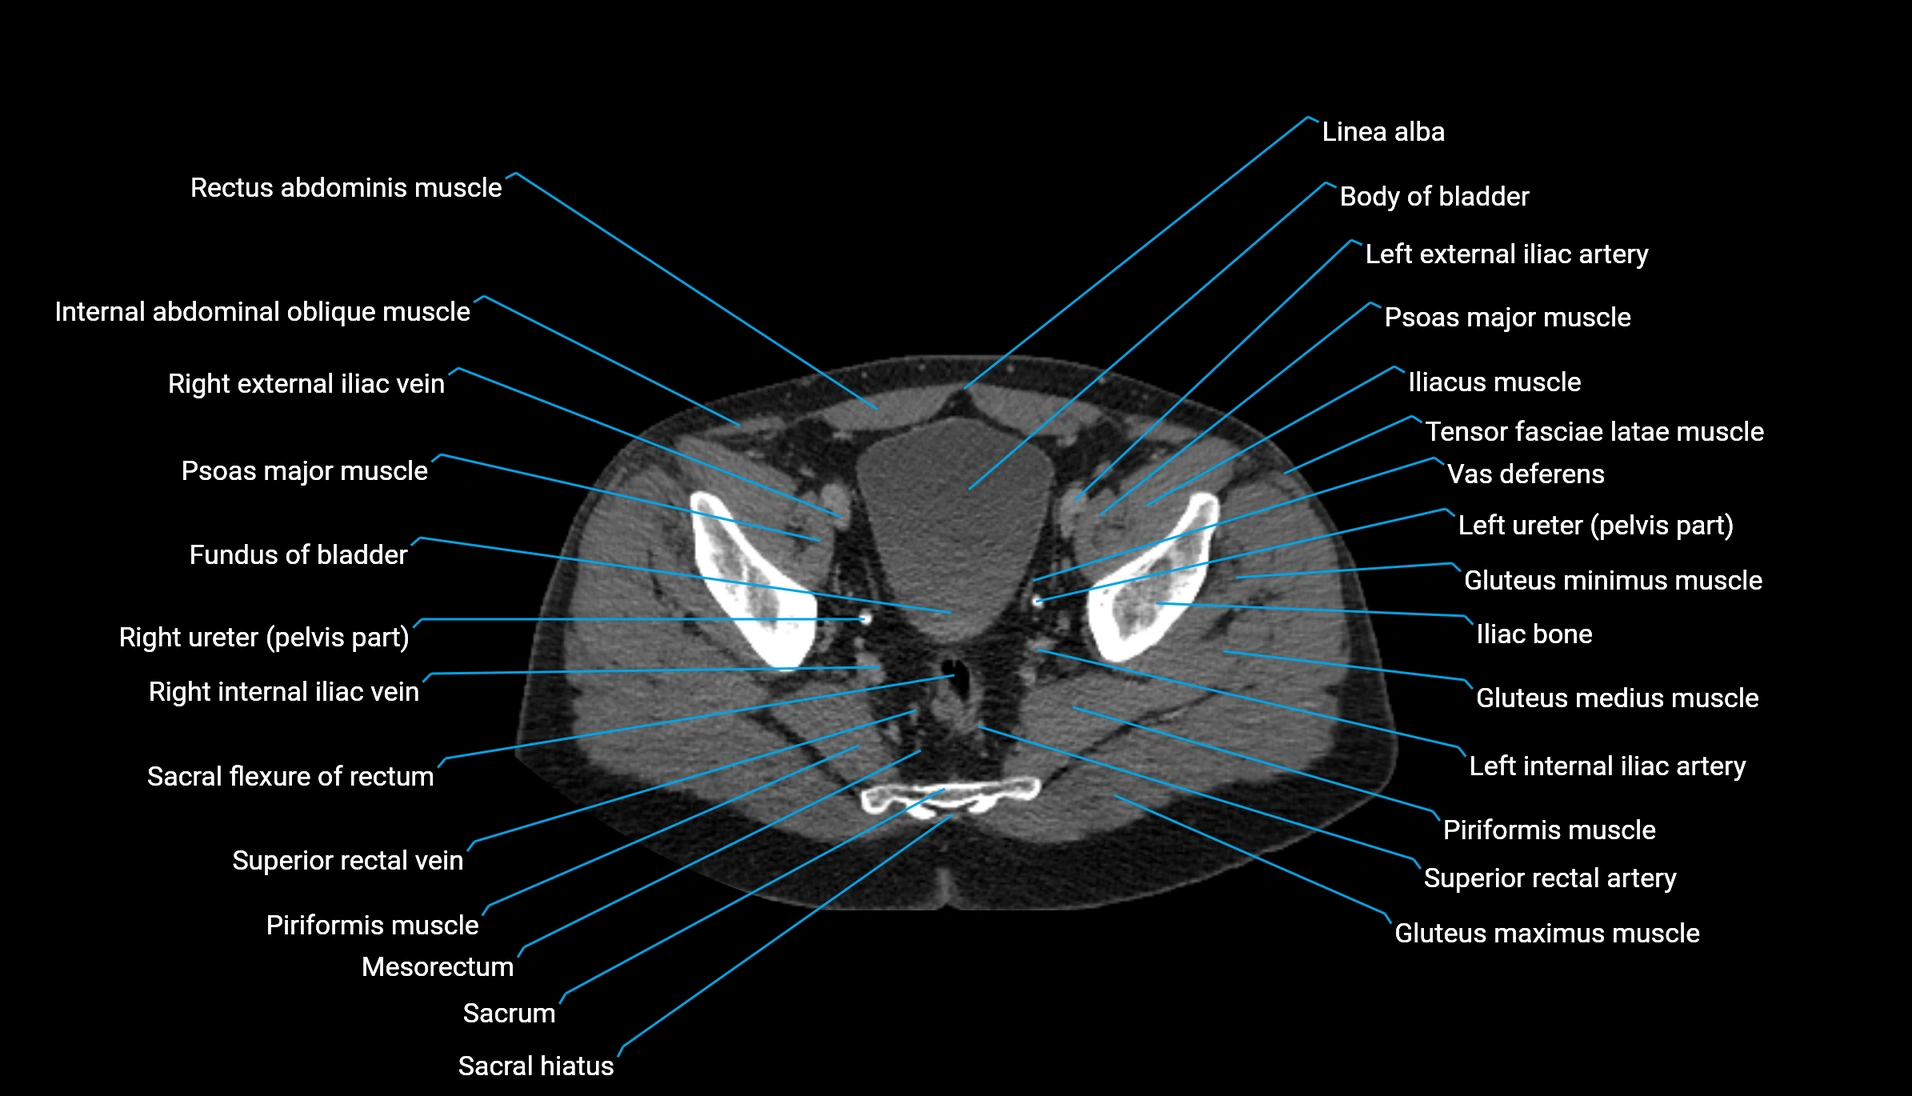

CT Appearance

Non-contrast CT:

-

Demonstrates cortical bone of acetabular rim in excellent detail

Detects fractures, dysplasia, retroversion, or bony overcoverage (pincer impingement)

3D reconstructions used in preoperative hip surgery planning

CT VRT 3D image

CT image